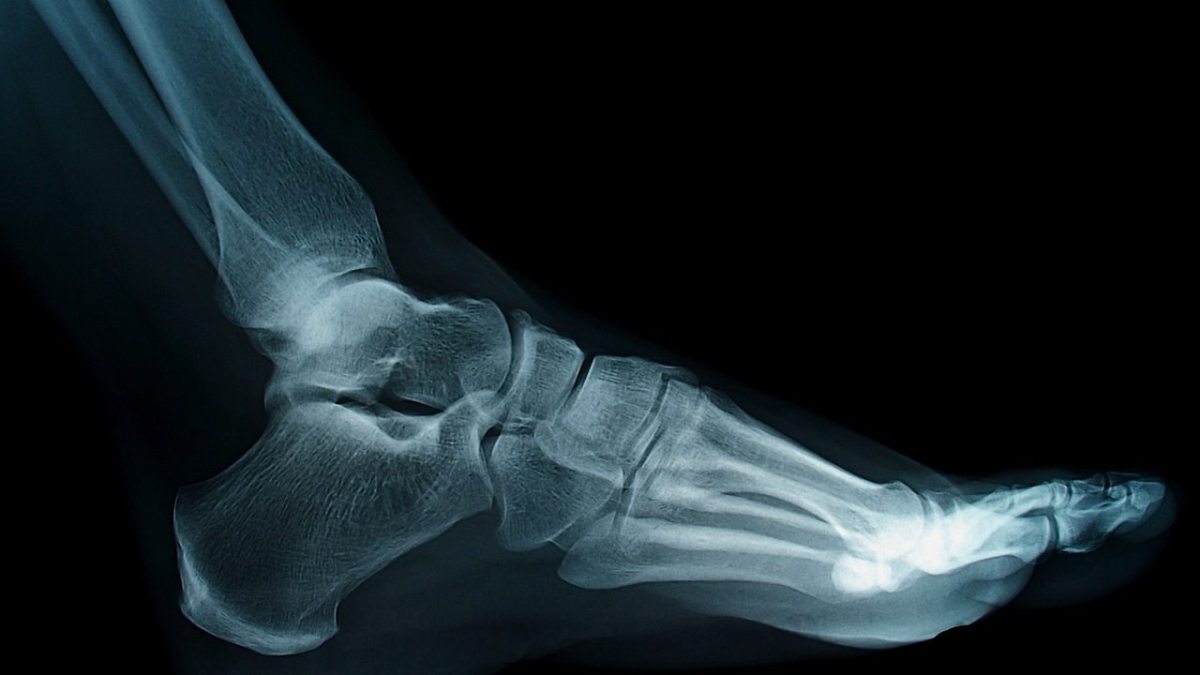

How To Determine If You Have Flat Feet . Typically, you can’t see an. Symptoms of flat feet depending on the cause of the flatfoot, a patient may experience one or more of the different. Having flat feet, also known as flatfoot, is a condition where one or both feet have little to no arch. People with flat feet or fallen arches either have no arch or a very low arch under their foot. When you stand, the pads of the feet press into the ground. Flatfeet can occur when the arches don't develop during childhood. In this guide, we’re sliding the socks off flat feet to uncover their causes and effects, as well as offering some viable solutions to help you understand how to correct flat feet and identify associated symptoms. When people with flatfeet stand up, the feet point outward, and the entire soles of the feet fall and touch the floor. Learn more about symptoms, causes, and treatment here. To view the mechanics of your feet, a health care provider will observe your feet from the front and back and ask you. Diagnosis of flat feet typically involves a visual examination of the foot, supported by imaging tests.